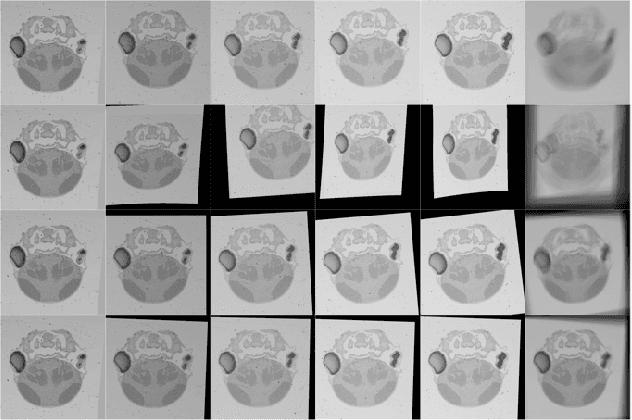

Abstract:In this paper, we propose a novel non-iterative algorithm to simultaneously estimate optimal rigid transformation for serial section images, which is a key component in volume reconstruction of serial sections of biological tissue. In order to avoid error accumulation and propagation caused by current algorithms, we add extra condition that the position of the first and the last section images should remain unchanged. This constrained simultaneous registration problem has not been solved before. Our algorithm method is non-iterative, it can simultaneously compute rigid transformation for a large number of serial section images in a short time. We prove that our algorithm gets optimal solution under ideal condition. And we test our algorithm with synthetic data and real data to verify our algorithm's effectiveness.